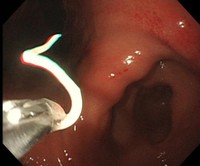

治療の第一選択は、内視鏡による摘出ですが、内視鏡は必要ないとの報告もあります。アレルギーを抑える注射と香蘇散という漢方薬で、ほとんどのアニサキス症を治療できるとの報告を見たことがあります。ただ、私は、万全を期すため一般的な内視鏡による摘出を第一選択としたいと思っています。